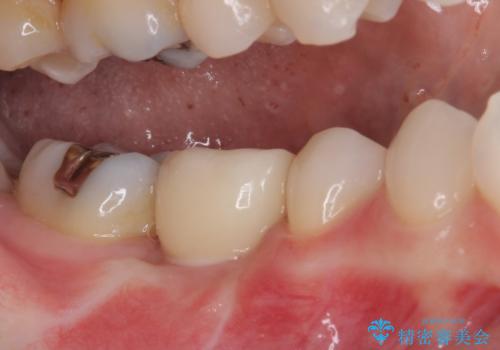

機能性と清掃性、更には審美性も考慮し、土台となるアバットメントにはジルコニアカスタムアバットメントを採用しました。

ジルコニアカスタムアバットメントは、歯肉ラインに金属が見えにくいというだけでなく、クラウンを装着する土台の形が天然歯と近い形態となるため、清掃性が高く歯肉が腫れにくいというメリットがあります。